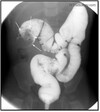

What pathology is shown here?

Cholelithiasis (Gallstones) -Seeing filling defects and huge blockage in the bile duct